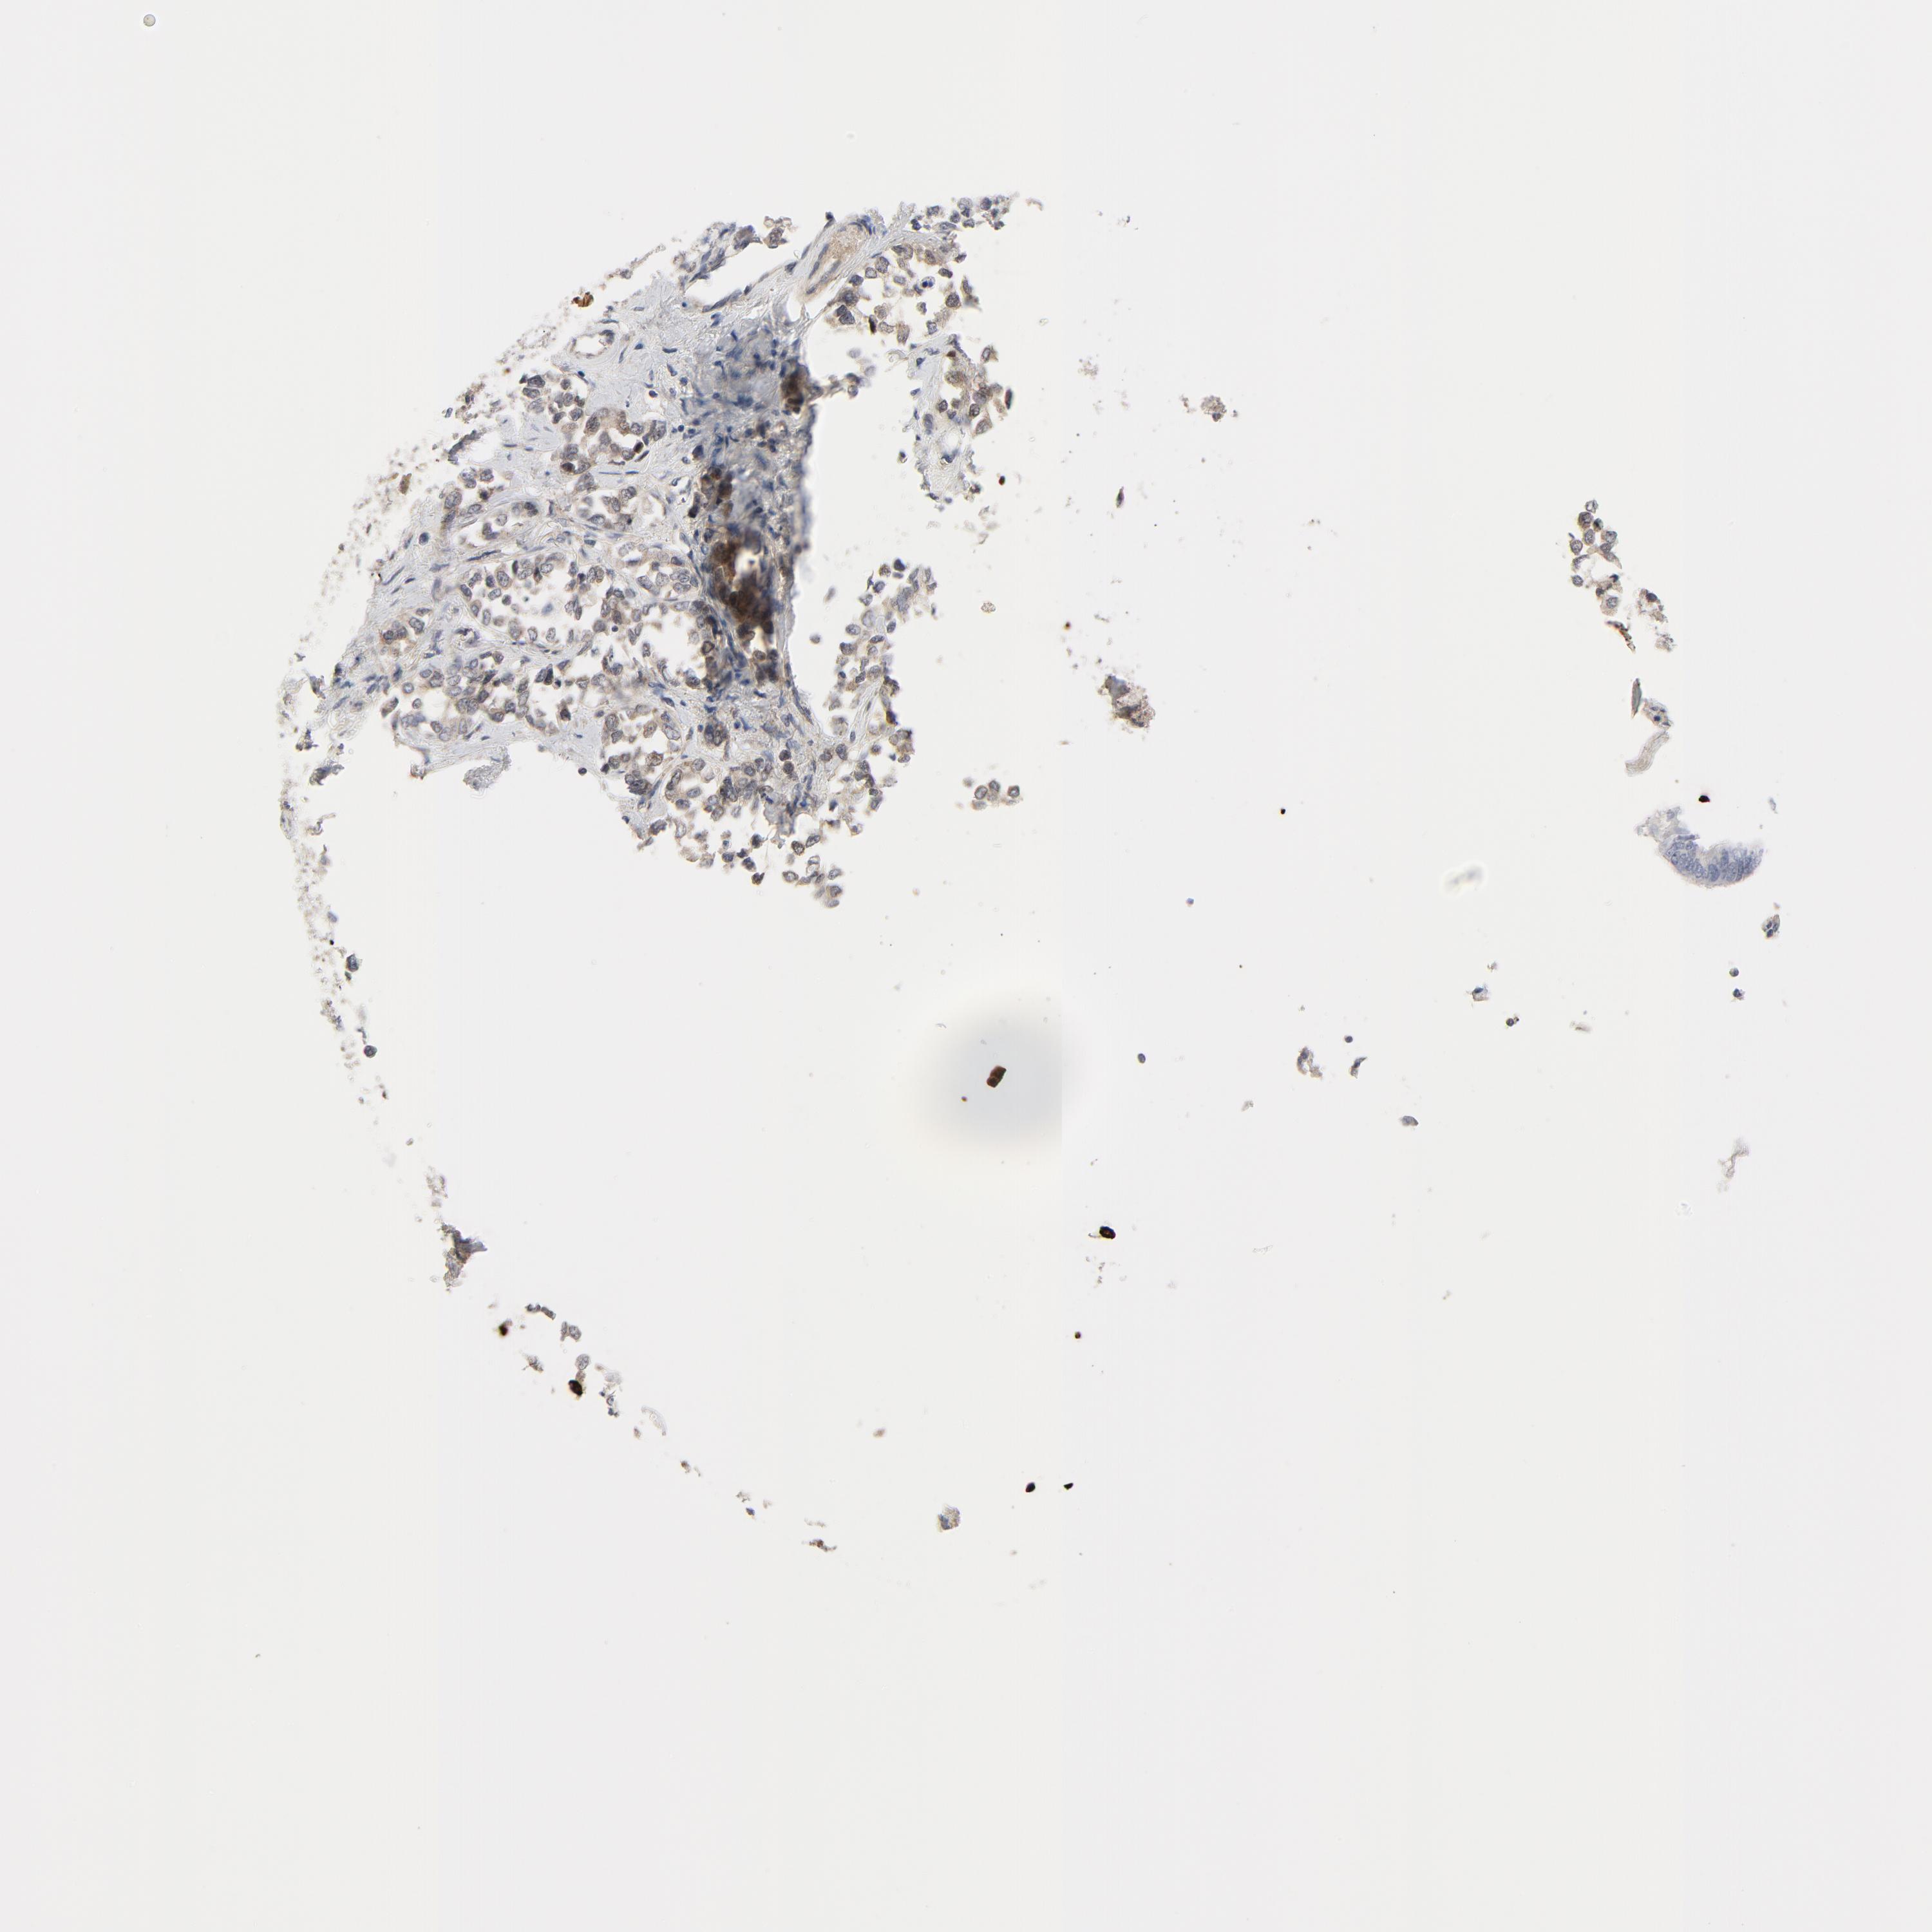

STOMACH CANCER - Protein expressioni

A mouse-over function shows sample information and annotation data. Click on an image to view it in a full screen mode. Samples can be filtered based on level of antibody staining by selecting one or several of the following categories: high, medium, low and not detected. The assay and annotation is described here.

Note that samples used for immunohistochemistry by the Human Protein Atlas do not correspond to samples in the TCGA dataset.

Antibody stainingi

Antibody staining in the annotated cell types in the current human tissue is reported as not detected, low, medium, or high, based on conventional immunohistochemistry profiling in selected tissues. This score is based on the combination of the staining intensity and fraction of stained cells.

Each image is clickable and will lead to virtual microscopy that enables deeper exploration of all samples and also displays staining intensity scores, fraction scores and subcellular localization as well as patient and tissue information for each sample.

Antibody HPA001633

Antibody CAB004262

Staining

High

Medium

Low

Not detected

Intensity

Strong

Moderate

Weak

Negative

Quantity

>75%

75%-25%

<25%

None

Location

Nuclear

Cytoplasmic/membranous

Cytoplasmic/membranous,nuclear

Adenocarcinoma, NOS

Adenocarcinoma, High grade